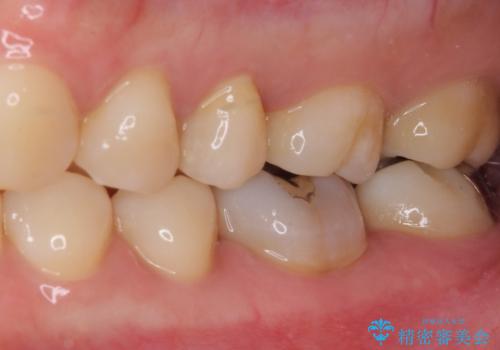

2歯ともに根管治療を行い、その後はオールセラミッククラウンにて補綴治療を行うこととしました。

来院時には食事が取れないほどの痛みを訴えていらっしゃいましたが、処置後からは痛みが軽減され、食事もいつも通りに取れるようになりました。